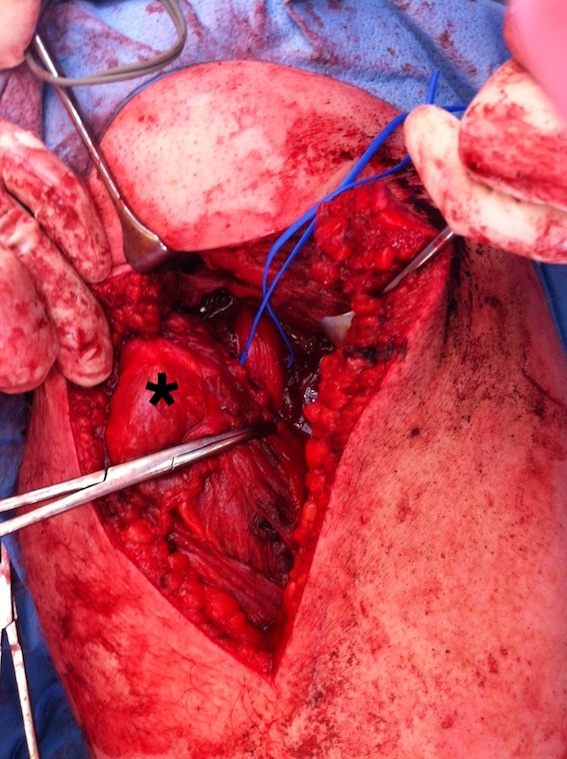

Hamstring (*) with sciatic nerve lateral to hamstring (blue vessiloop)

Identify and release proximal hamstring tendon

Stump of the conjoint tendon (*)